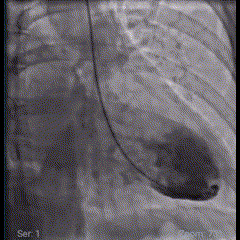

Agora, vamos à imagem da semana:

Um clássico é um clássico: bela imagem de ventriculografia de um paciente com síndrome de Takotsubo, caracterizada pela acinesia dos segmentos das porções médio e apical, e hipercinesia basal.